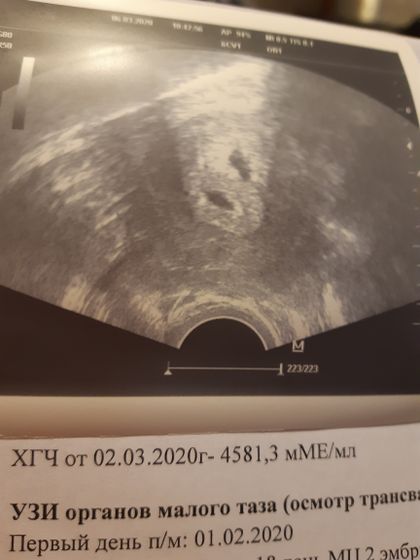

Угрозы нет, отслоек не визуализируется, в полости матки сухо! Лежать, не нервничать, следовать рекомендациям! Я рада, что оба малыша со мной!??????